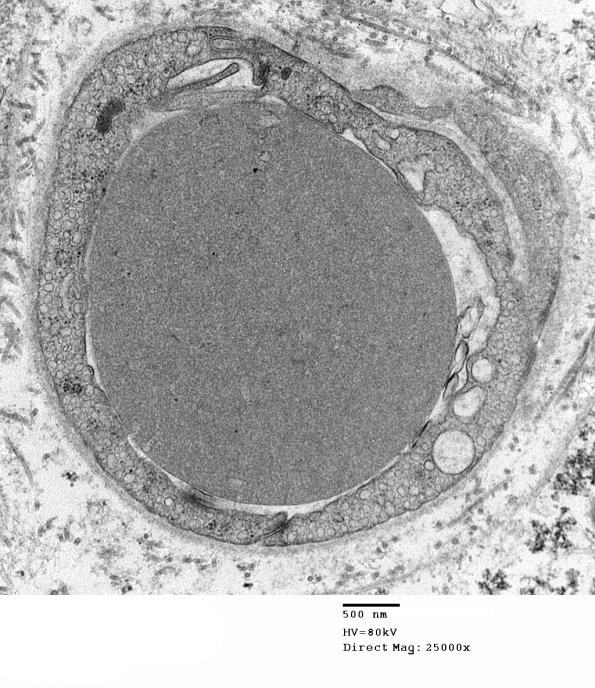

3A1 Normal Sural nerve, 3 mo age (Case 3) 015 - Copy

A capillary with an intravascular red cell.